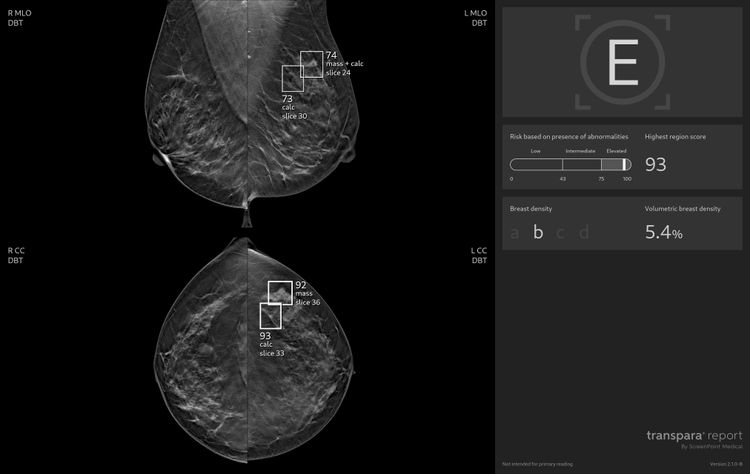

ScreenPoint Medical uit Nijmegen ontwikkelde Transpara, AI-software die radiologen ondersteunt bij het beoordelen van mammografiebeelden. Transpara analyseert elk beeld tot in detail, wijst radiologen op mogelijke afwijkingen en biedt een risicoscore per patiënt. Daarmee vergroot de software de kans dat tumoren vroegtijdig worden ontdekt.

Sinds de oprichting in 2014 door professoren Nico Karssemeijer en Michael Brady heeft het bedrijf een sterke internationale positie opgebouwd. Transpara ondersteunt inmiddels duizenden radiologen wereldwijd, met als doel vrouwen sneller en beter helpen door betrouwbare, geautomatiseerde ondersteuning bij borstkankerscreening.

Vorig jaar toonde Zweeds onderzoek aan dat Transpara meer borstkankers detecteert zonder fout-positieve percentages te verhogen. Oost NL is sinds 2016 aandeelhouder van ScreenPoint Medical.